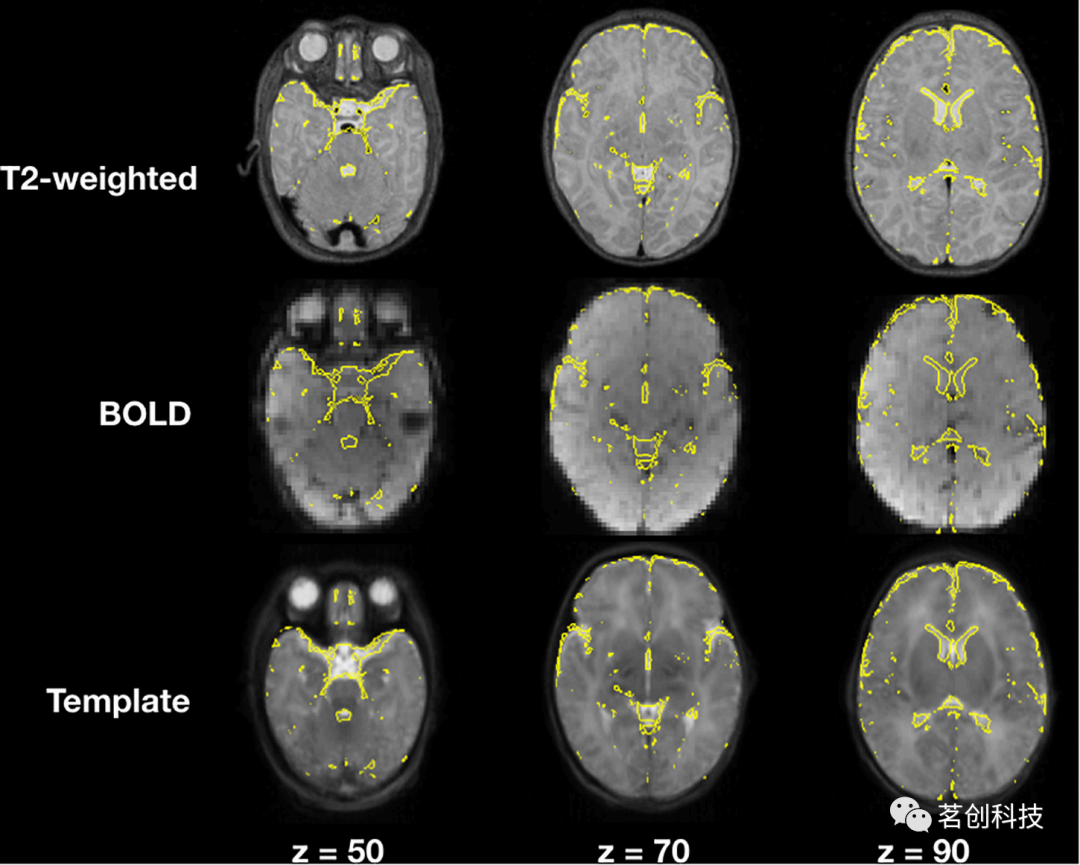

图像配准

图4展示了一个代表性被试的T2加权图像和BOLD图像以及与模板的配准结果。黄线代表分割的脑脊液。目视检查后,观察到每个测试被试的两种配准在模板内的正确对齐。

图4.立体定向空间的T2加权和BOLD图像的配准。

当比较rsfMRI的单步配准与两步配准方法时,两者之间没有明显差异,最终功能连接结果呈现相同的相关性强度和拓扑结构。这两种方法的主要区别在于计算时间不同,两步配准法的计算时间成本更高。